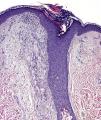

El estudio histopatológico de una pápula localizada en la región preesternal inferior reveló la presencia de dilatación y taponamiento hiperqueratósico del infundíbulo piloso, que se encontraba circundado por abundantes histiocitos espumosos (macrófagos xantomizados) (fig. 2), una respuesta inflamatoria crónica linfocitaria perianexial de leve a moderada intensidad y grupos glandulares apocrinos entre la dermis reticular y la hipodermis, con tendencia a la dilatación quística (fig. 3).

Los hallazgos histopatológicos que definen la EFF son variados, habiéndose descrito: la dilatación e hiperqueratosis del infundíbulo folicular, la espongiosis y la disqueratosis del epitelio infundibular, la degeneración vacuolar de la unión dermoepidérmica, la presencia de un infiltrado inflamatorio linfocitario perianexial, la paraqueratosis en el epitelio infundibular en forma de laminillas cornoides, la dilatación de las glándulas apocrinas y la xantomatosis perifolicular, que es considerada como uno de los hallazgos más característicos3,8,9.